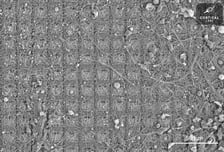

AI 칩에 인간 뇌 세포 붙였더니 전력 효율 '쑥"[월드콘]